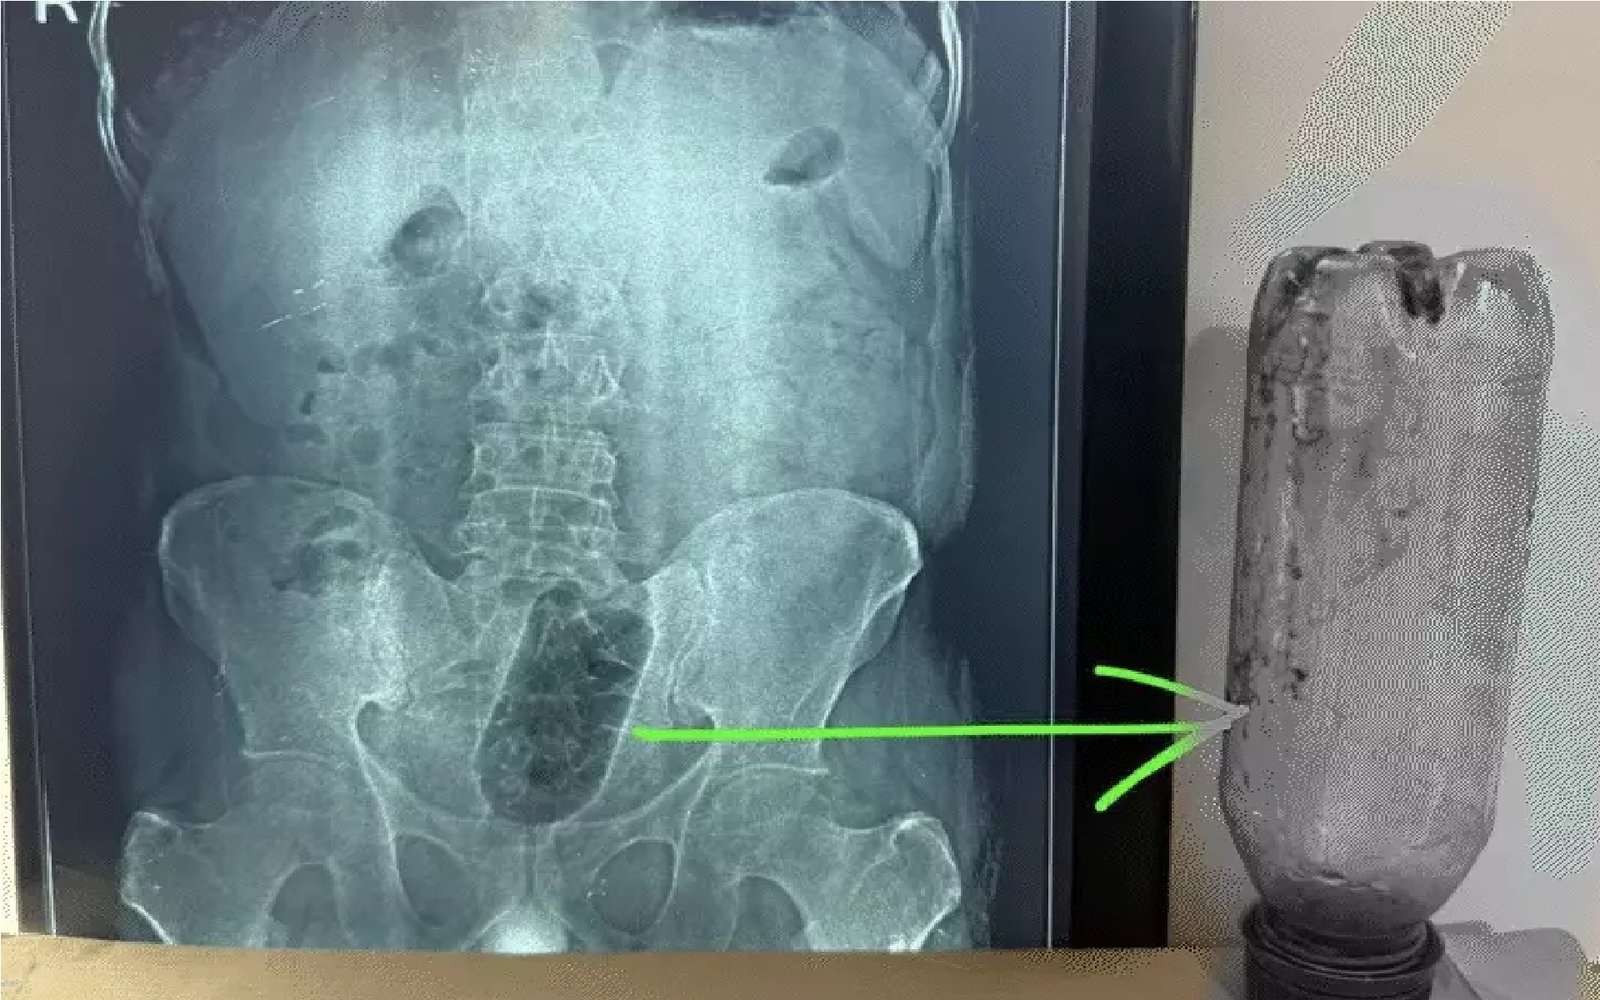

परिवार के लोगों ने जब उसे कमरे में दर्द से कराहते हुए देखा तो तुरंत पास के एक निजी अस्पताल में भर्ती कराया। डॉक्टरों ने एक्स-रे जांच कराई तो मलद्वार के पास बोतल फंसी होने की पुष्टि हुई। इसके बाद युवक को इमरजेंसी में भर्ती कर ऑपरेशन की तैयारी की गई।

अस्पताल के सर्जनों की टीम ने सावधानी के साथ करीब एक घंटे से अधिक समय तक सर्जरी की। ऑपरेशन के दौरान खास ध्यान रखा गया कि बोतल निकालते समय मलाशय को कोई गंभीर नुकसान न पहुंचे। सफल सर्जरी के बाद बोतल को बाहर निकाल लिया गया और युवक की हालत स्थिर बताई गई। डॉक्टरों के अनुसार युवक को चार दिन तक अस्पताल में निगरानी में रखा गया। इस दौरान सिग्मोइडोस्कोपी के जरिए मलाशय की जांच भी की गई। घाव भरने के बाद और शौच संबंधी कोई दिक्कत न होने पर डॉक्टरों ने उसे छुट्टी दे दी।